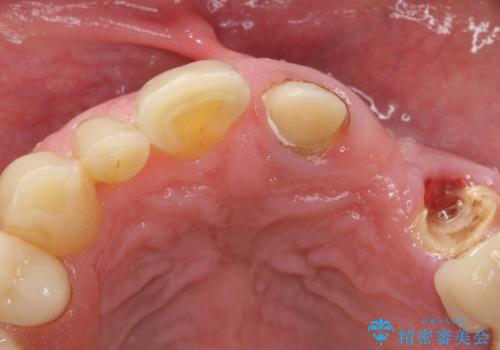

- ブリッジの支台歯であった左上の犬歯が折れたことを主訴に来院された患者様です。

犬歯は歯ぐきの奥深くまで割れており保存不可能な状態でしたが、どうしても抜きたくないとのことでした。

歯を牽引し健全歯質を歯肉縁上まで引き上げ、歯の保存を試みることにしました。